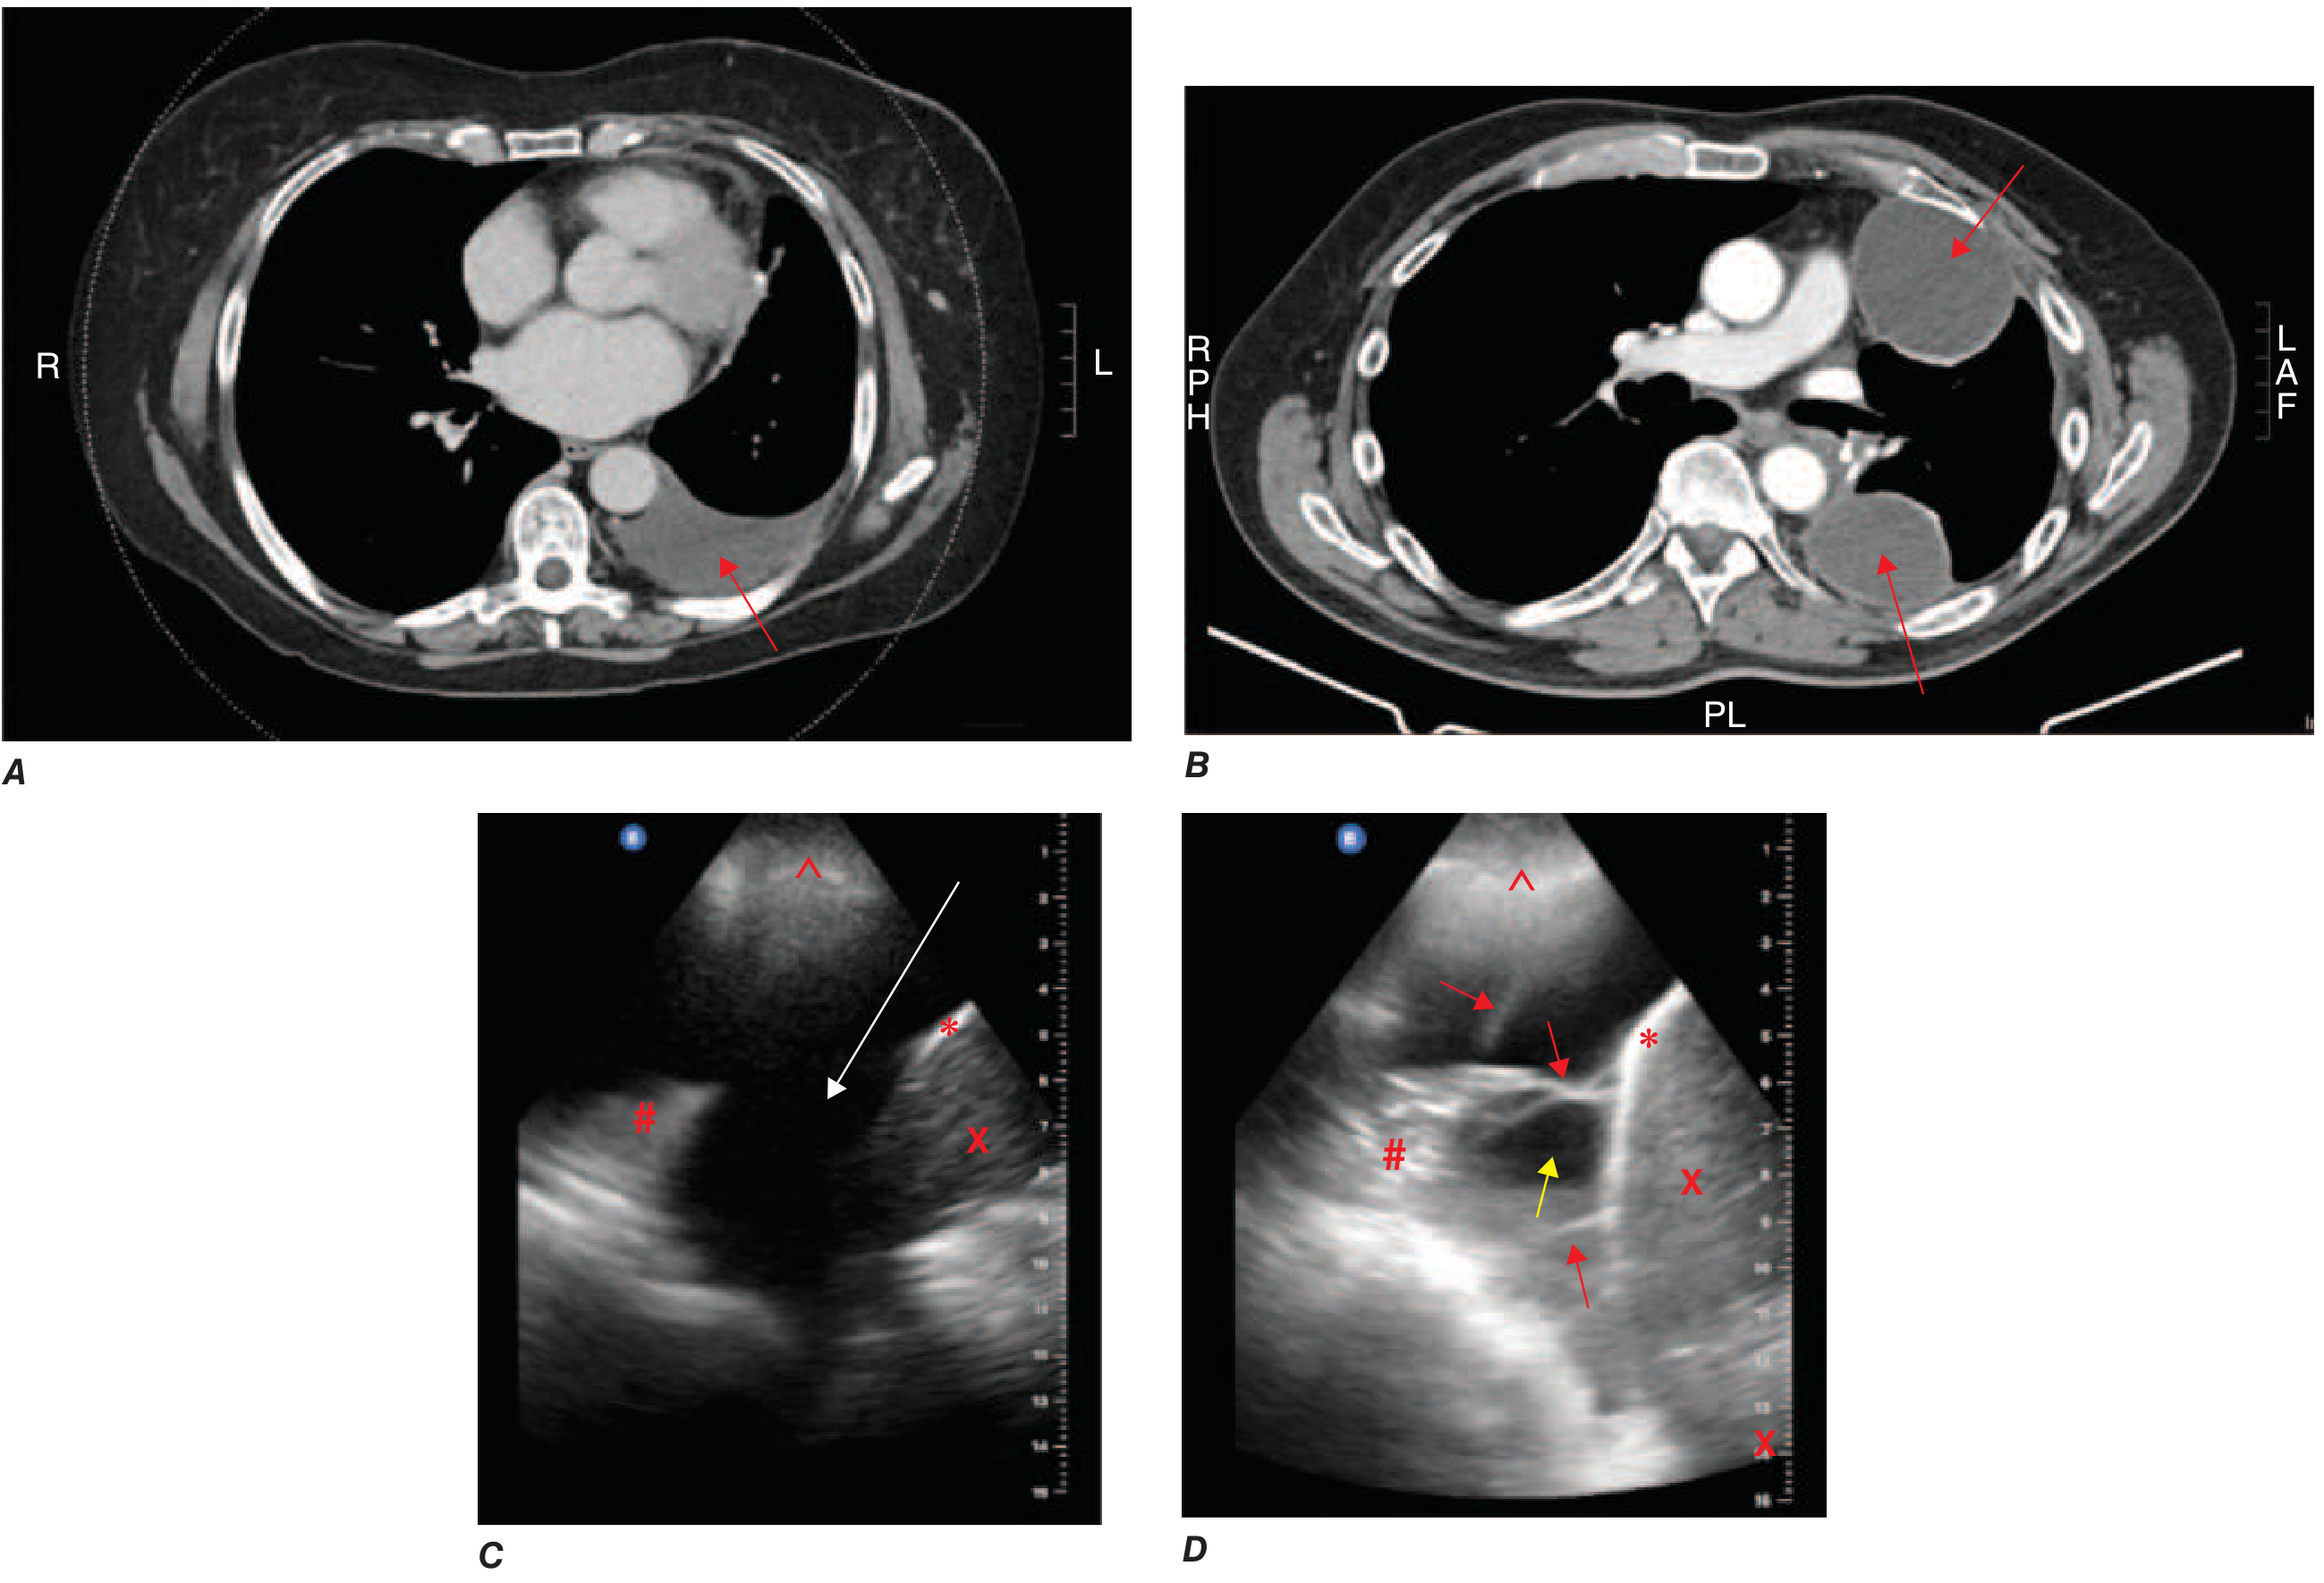

CT and ultrasound of simple vs. loculated pleural effusion

A: CT — simple free-flowing left effusion (red arrow). B: CT — loculated effusion with two pockets. C: Ultrasound — simple effusion. D: Ultrasound — complex effusion with septations — Harrison's Principles of Internal Medicine